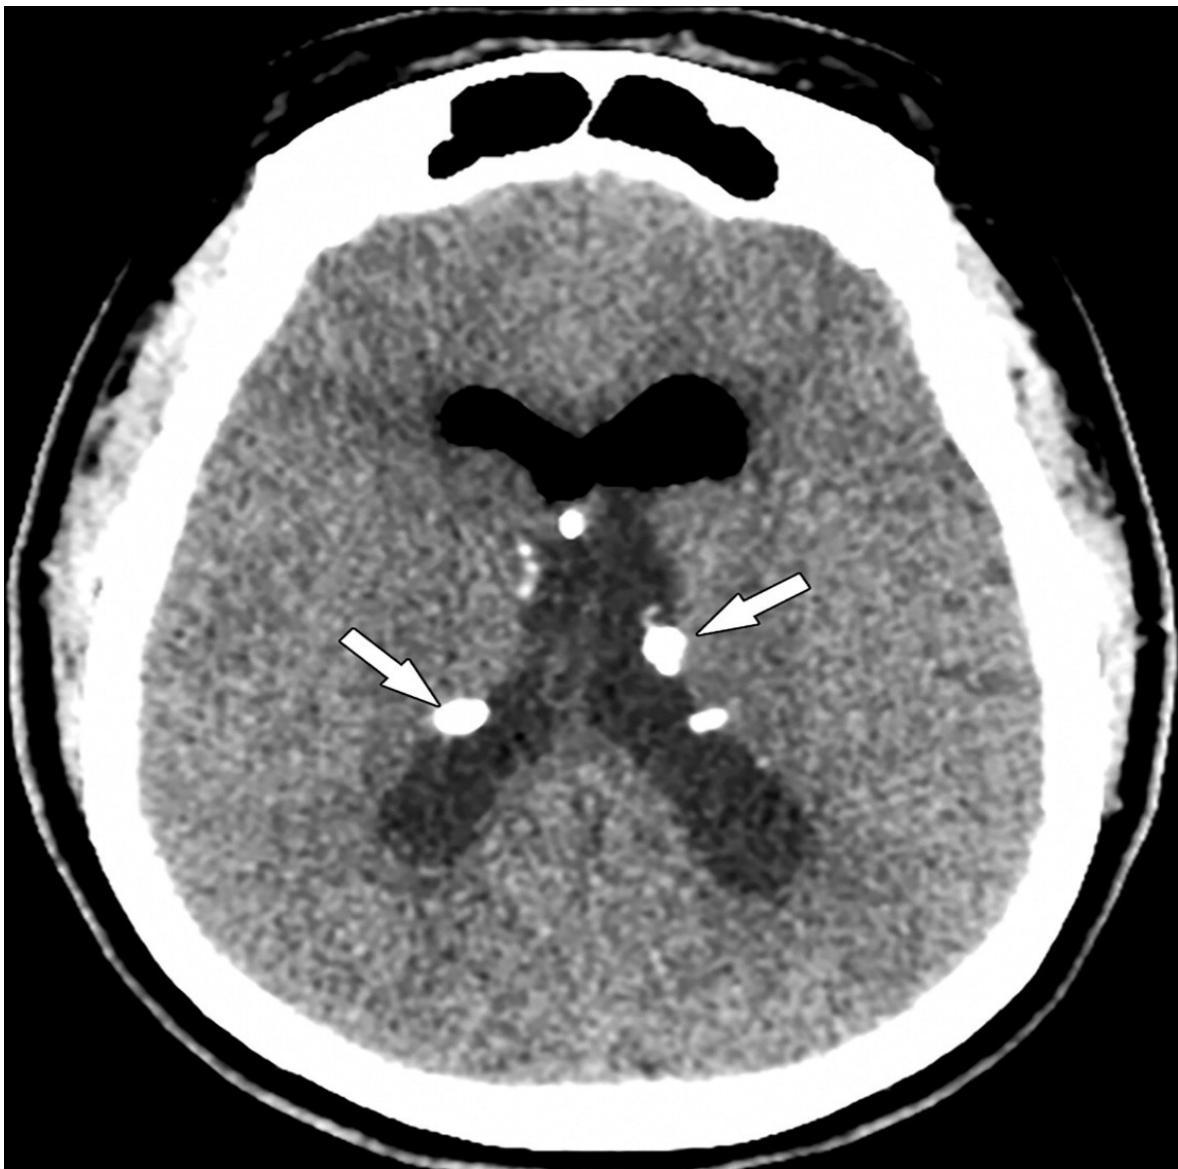

- Subependymal Nodules: Calcified nodules adjacent to lateral ventricles (Hamartomas).

Subependymal calcification:

- Subependymal nodules

Diagnosis: Based on characteristic lesions, seizures, intellectual deficit, and visceral tumors. Neuroimaging (MRI) demonstrates subependymal-calcified nodules.